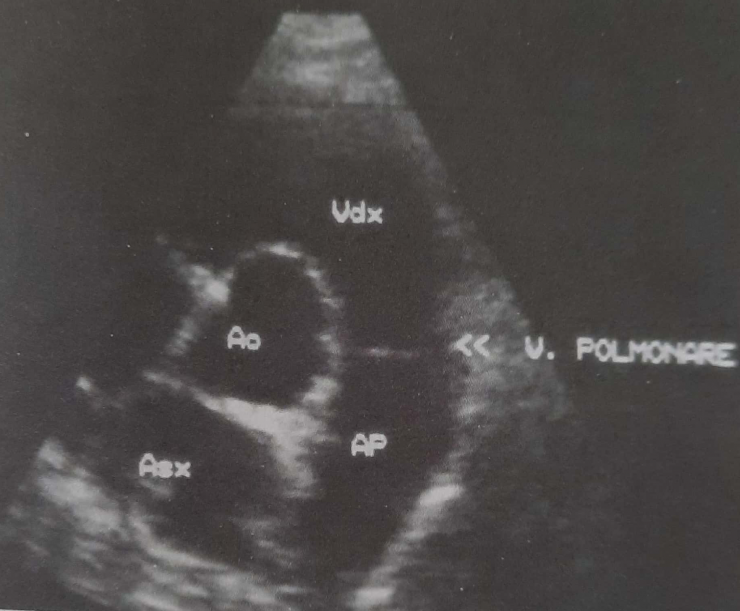

Plani (prerja) i skanimit lehtësisht mbi bazën e zemrës (majtas). Ky seksion siguron vlerësimin ekografik të valvulës pulmunare. AP = arteria pulmonare; Ao = aorta; Asx = atriumi i majtë; Vdx = ventrikuli i djathtë; V. Polmonare = valvula pulmonare.